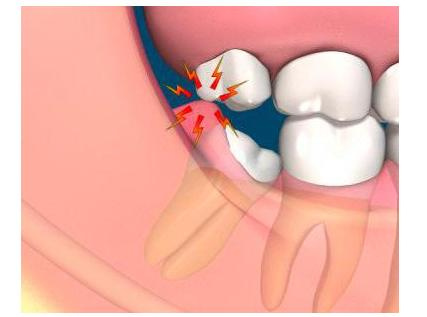

La gingivitis es la inflamación de las encías debido a la acumulación del sarro entre diente y encía provocando la inflamación de las mismas y el sangrado. Si la enfermedad no se resuelve a tiempo y la infección sigue su evolución puede derivar en una periodontitis. En esta fase las encías se retraen y puede dañar el hueso que soporta el diente y favorecer su pérdida.